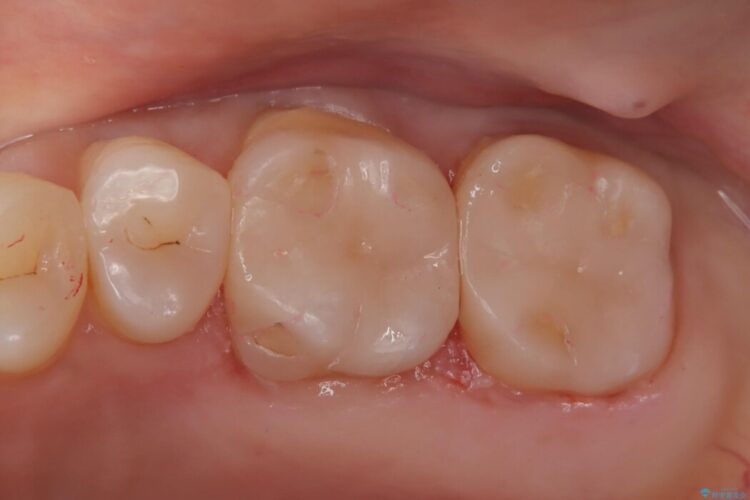

金属の詰め物を除去して虫歯の処置をした後にセラミックインレーにて修復しました。

セラミックは天然歯に近い見た目であるため目立たず、劣化しにくいことが特徴です。

見た目、噛み合わせなどご満足いただけました。